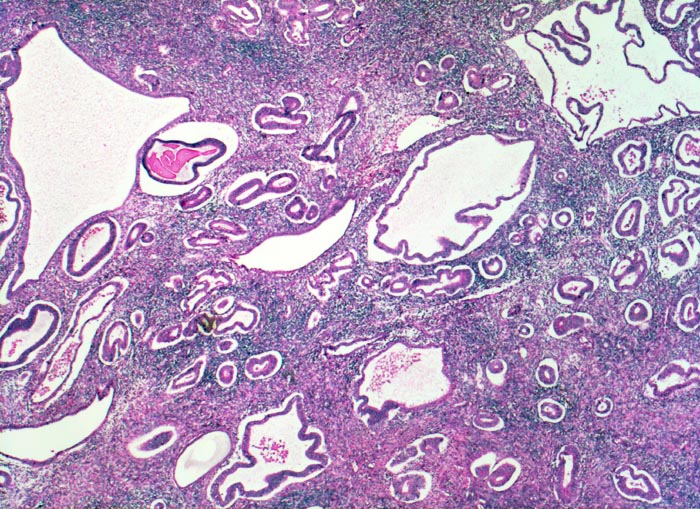

glandulär zystische Hyperplasie der Korpusmukosa

Hoch aufgebaute Mukosa mit unregelmässig zystisch dilatierten Drüsen (sogenanntes Schweizerkäsemuster). Zwischen den einzelnen Drüsen liegt reichlich Stroma.

Meno-Metrorrhagien bei perimenopausaler Patientin. Adipositas.

Die Endometriumhyperplasie wird eingeteilt in eine einfache Hyperplasie mit oder ohne Atypie (meist ohne Atypie) oder eine komplexe Hyperplasie mit oder ohne Atypie. Die vorliegende einfache Hyperplasie entwickelt sich nur selten zu einem Endometriumkarzinom weiter.